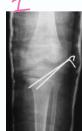

Extra-articular (Type I / II)

- Stable: conservative

- Unstable: K-wire / screws with cast

Case Example: 12-year-old male, Salter-Harris Type II